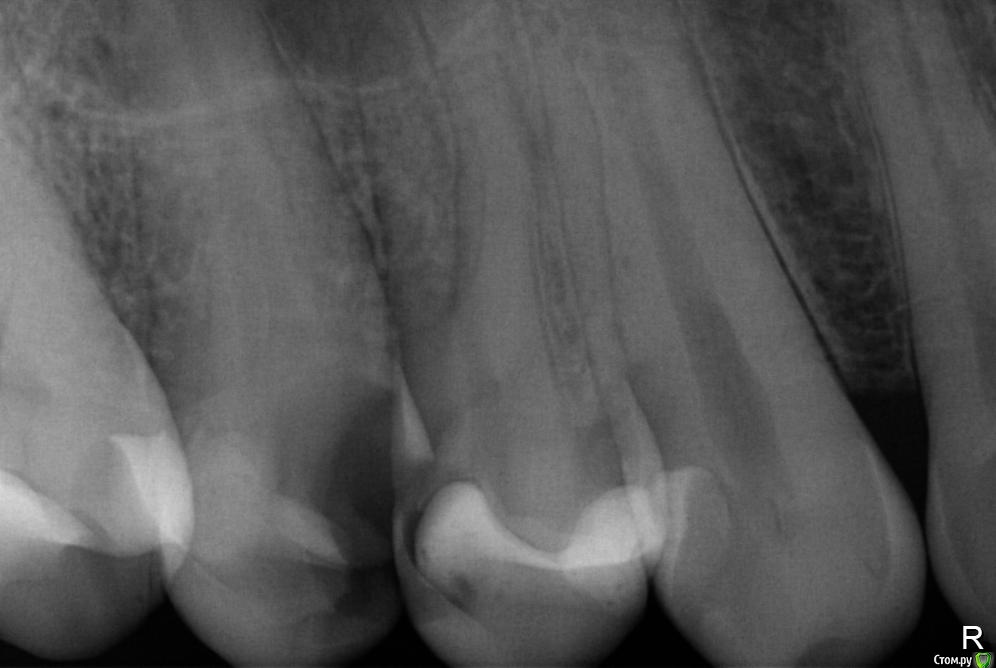

Хронический пульпит - уточнение плана лечения

Мне поставили диагноз -- хронический пульпит. Вот снимок. Сказали, что стоимость лечение такого зуба составит 10 тысяч рублей.

Прилагаю прицельный снимок 1.4